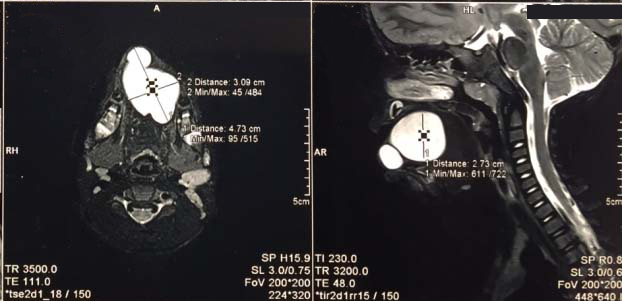

A three-year-old male child presented at the ENT Department of Lok Nayak Hospital, Delhi with a history of diffuse swelling in the tongue since two months. The swelling was progressively enlarging, slightly tender, causing difficulty in mastication. Apart from these no other symptoms were present. The swelling was present over the dorsal aspect involving the anterior half of the tongue measuring approximately 2x2 cm [Table/Fig-1]. No past history of trauma or significant dental complaints was present. On examination, the swelling was cystic and soft in consistency. Magnetic resonance imaging was performed, which revealed a well defined cystic lesion with internal septae and peripheral enhancement in tongue and lower lip [Table/Fig-2]. Differential diagnosis of epidermoid cyst and lymphangioma were considered. The swelling was excised and sent to histopathology department. Grossly, a cyst measuring 2.5cm in diameter was identified with wall thickness of 0.2cm. Microscopic examination showed a cyst lined by stratified squamous epithelium, with keratinous flakes and large areas of surface ulceration; ulcer bed was formed by acute and chronic inflammatory granulation tissue comprised of neutrophils, lymphocytes and occasional plasma cells. No mitosis, necrosis or atypia was present [Table/Fig-3]. No evidence of malignancy was seen. No hair shaft or other dermal appendages were identified. A confirmatory diagnosis of ruptured and inflamed EIC tongue was given.

Well defined cystic lesion with internal septae.